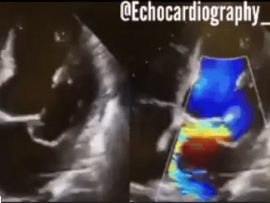

Lee masSevere Mitral Stenosis and Moderate Aortic Regurgitation Mohammed Zidan, MBBCH, M.Sc Cardiology (Cardiology, Echocardiography and interventional Cardilogy Specialist at Al-Azhar university), Cairo, Egypt.

Lee masParavalvular Leakage at 3 o’clock of Mitral Valve. Mohammed Zidan, MBBCH, M.Sc Cardiology (Cardiology, Echocardiography and interventional Cardilogy Specialist at Al-Azhar university), Cairo, Egypt.